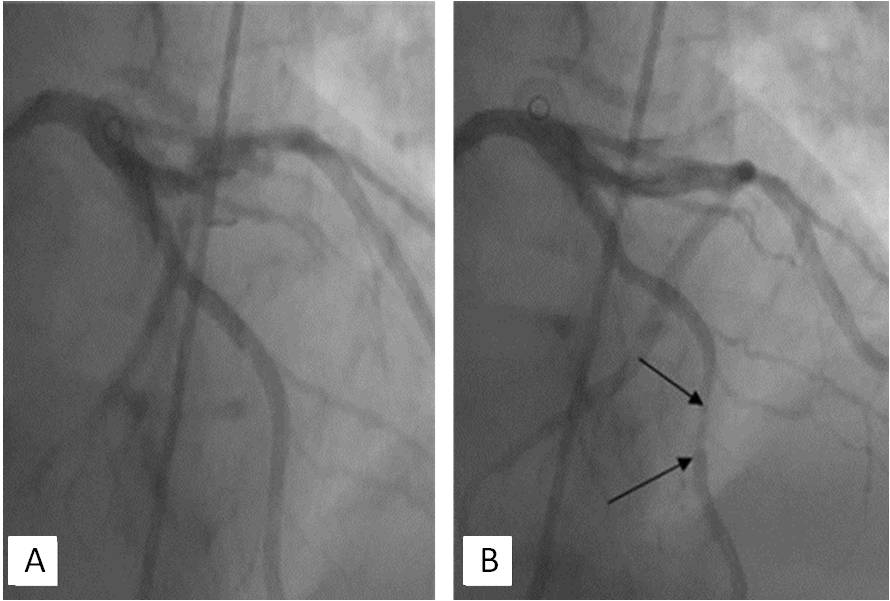

Coronary angiography (11/12/2014). Left type of circulation. The left CA trunk without changes. МB in the middle AIVA segment narrowing the lumen of the artery to 80% in systole (Figure 3). Stenosis of the orifice of the 1st diagonal branch to 60%, stenosis of the middle segment of circumflex artery to 50%. The right CA without changes.

Fig. 3. Coronary angiography (11/12/2014) of patient L. A myocardial bridge in the middle segment of the anterior interventricular artery (diastole (A), systole (B)) with compression of the artery in systole to 80% (arrows).